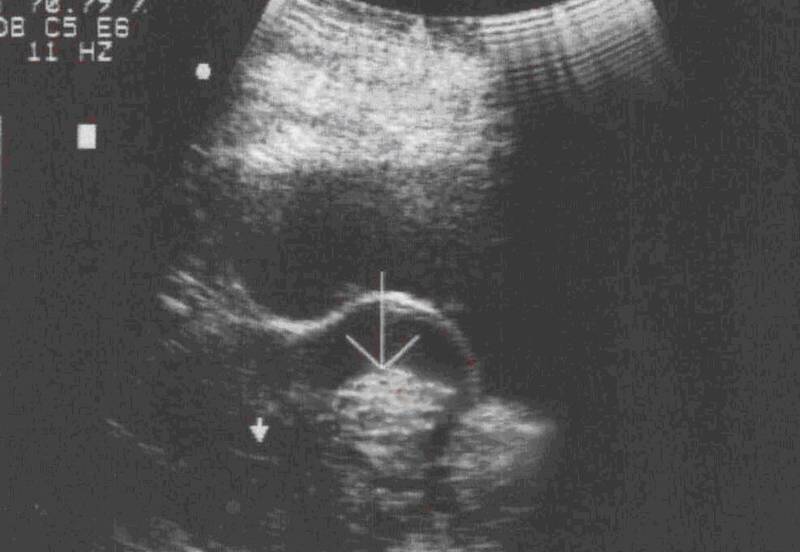

Обычно на фото при УЗИ выявляются увеличенные размеры главного женского органа и возникновение в маточной полости сгустка округлой формы, который, к тому же, хорошо проводит звук. Если матка на фото УЗИ изменила свою форму, значит, миоматозные узлы достигли уже весьма приличных размеров.

Стоит отметить, что миома матки фото на УЗИ будет выглядеть как совершенно иная от матки структура. Размеры ее обычно указываются в неделях беременности, который будет свидетельствовать на самом деле о размере главного женского органа, соответствующего сроку вынашивания ребенка.

Фото 1. Как выглядит миома матки на УЗИ.

Врач-сонолог определяет миому как округлый объект с гетерогенной структурой и чёткими границами, делающими сигнал датчика слабее.

На снимке хорошо видна интрамуральная миома и эмбрион. Предполагаемый срок беременности – 5-6 недель. Миома не выходит в полость матки и на данном этапе не мешает развитию плода: